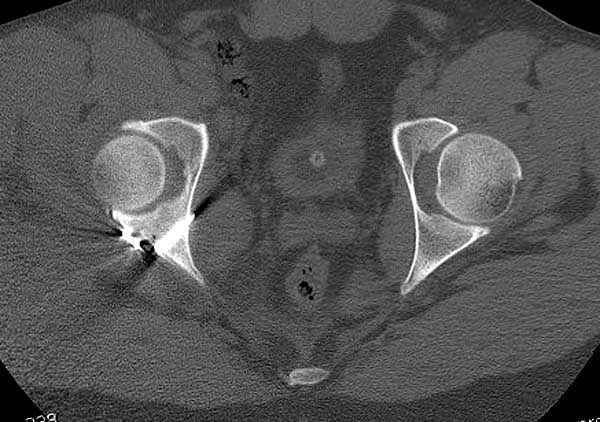

5:24 Рентгенограмма таза, вызывают врача ортопеда (снимок N1), его диагноз: закрытый переломо-вывих правого тазабедренного сустава, получает добро на закрытую репозицию в приемном отделении

11:50 больной в послеоперационной, рентгенограмма N7, компьютерная томограмма в тот же день N8-10